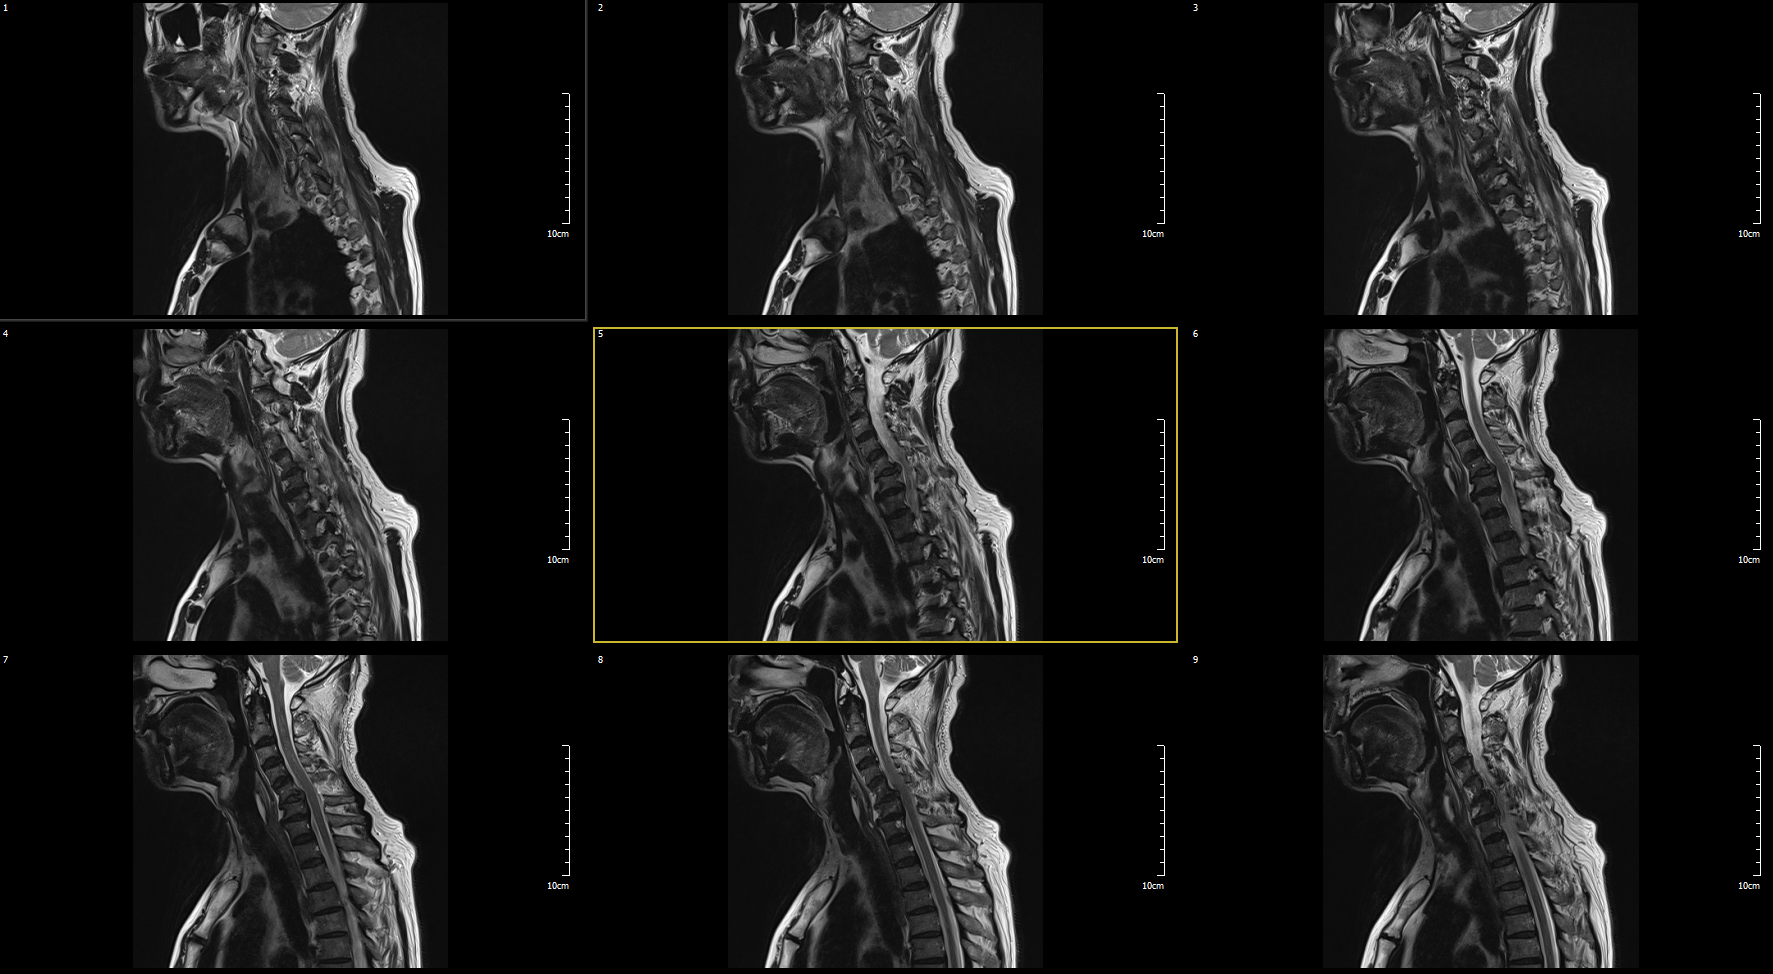

MRI

C5-6 : Ruptured HCD, Rt